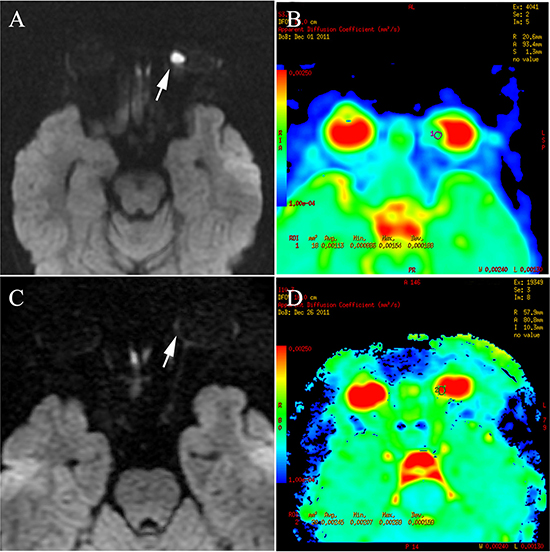

Figure 4: Retinoblastoma of the right eyeball in a 44-month-old female (patient 2). The DWI (A) shows hyperintensity in the tumor (arrow), indicating hyper-cellularity. The apparent diffusion coefficient (ADC) of this lesion was 1.13 × 10−3 mm2/s (B). After three cycles of intra-arterial chemotherapy (IAC), DWI shows hypointensity in the tumor region (C), with ADC of 2.45 × 10−3 mm2/s (D).

The ADC values of all tumors before IAC were < 1.55 × 10−3 mm2/s and 90% were < 1.30 × 10−3 mm2/s (Figure 4). The mean ADC value of the tumors before IAC was 0.94 ± 0.24 × 10−3 mm2/s. Ninety-two percent (55/60) of the tumors after IAC showed higher ADC values of > 1.90 × 10−3 mm2/s (Figure 4), with a mean ADC of 2.24 ± 0.40 × 10−3 mm2/s. Only three of 60 retinoblastoma patients after IAC had an ADC of < 1.55 × 10−3 mm2/s, which approached the value of the greatest ADC before IAC. The differences in ADC values before and after IAC were significant (t = −23.76; P < 0.001) as shown in Table 2.

The differences in ADC values of group D or group E were significant (t = 21.95; P < 0.001 and t = 13.5; P < 0.001) as is shown in Table 2. However, there was no significant difference between the patients in group D and group E regarding the ADC values before or after treatment (P > 0.001).

Noninvasive DWI has been used to evaluate therapy responses in animal models and humans [16, 31]. Some studies of animal models [31–33] and clinical studies [16, 34] have shown an increase in ADC after variable therapeutic modalities. It is believed that cellular damage leading to necrosis contributed to increased ADCs [35, 36]. In our study, the results showed significant increases in ADCs of all tumors after IAC. Most residual tumor foci showed an ADC > 1.90 × 10−3 mm2/s, indicating low cell density. There were three cases with ADC values after IAC overlapping the range of the greatest ADC value before IAC. In those cases, the clinical examination and contrast-enhancing T1-weighted imaging data should be weighted appropriately to more accurately determine the activity of the tumor. In our study, one of three cases showed non-enhancement, and the others showed mild enhancement. However, at > 6 months follow-up, using monthly funduscopy, no relapse or recurrence was noted. We suggest that the relatively low ADC value of the residual tumor foci after treatment may be due to the fluid in the retina encapsulating the residual tumor or necrotic tumor tissue due to therapy. A recent study [14] has shown an intermediate ADC value [1.47 (0.99–1.80) × 10−3 mm2/s] in the necrotic tumor tissue and low ADC values [1.03 (0.72–1.22) ×10−3 mm2/s] in viable tumor tissues of retinoblastoma patients, further supporting our results.